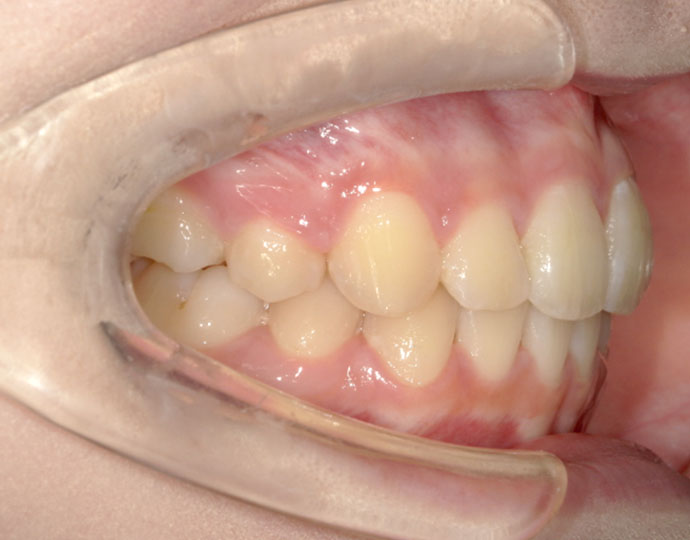

治療後

| 患者様 | 女性 18歳 |

| 主訴 | 歯並びを綺麗にしたい。 |

| 診断 | 叢生歯列不正咬合 |

| 治療方針 | 上下顎左右第一小臼歯の抜歯(計4歯) |

| 治療に使用した装置 | セルフライゲーションブラケット(インタラクティブタイプ) |

| 治療期間 | 2年2カ月 |

| 治療回数 | 24回 |

| 治療費(自費診療) | 847,000円(税込み) |